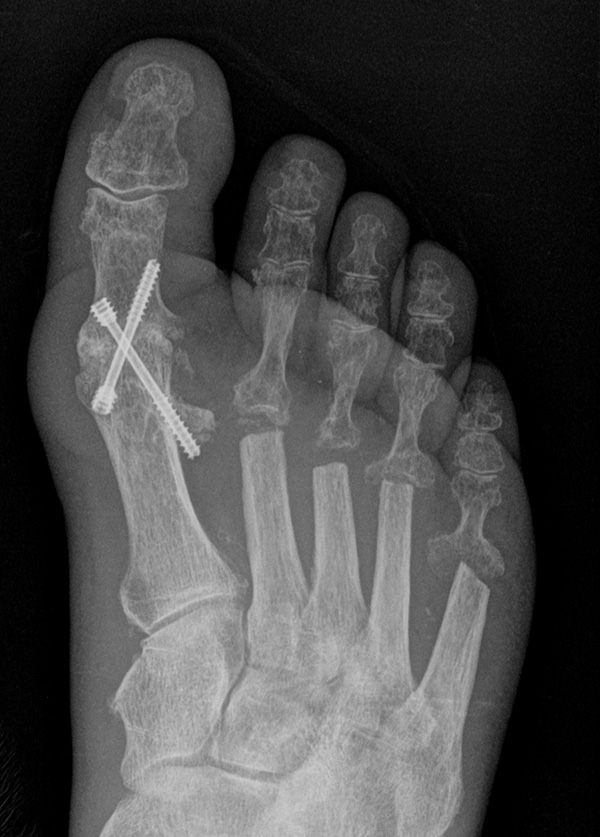

Deutlich bessere Ergebnisse wurden erreicht durch eine Kombination der OP nach Tillmann mit einer Arthrodese des Großzehengrundgelenks oder auch einer Lapidus-Arthrodese 611. Dies wurde bereits 1956 durch Vainio empfohlen, hat sich aber erst in diesem Jahrtausend flächendeckend durchgesetzt 121314.